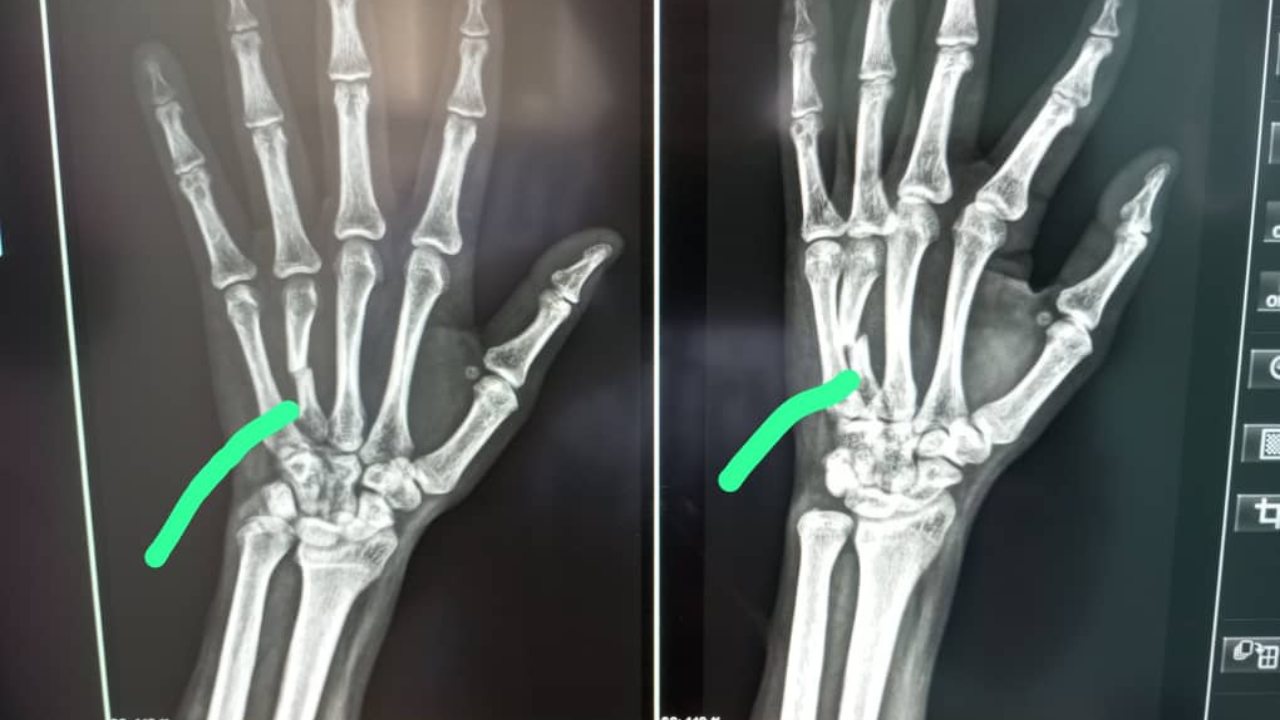

Een gebroken arm die niet wordt geopereerd.